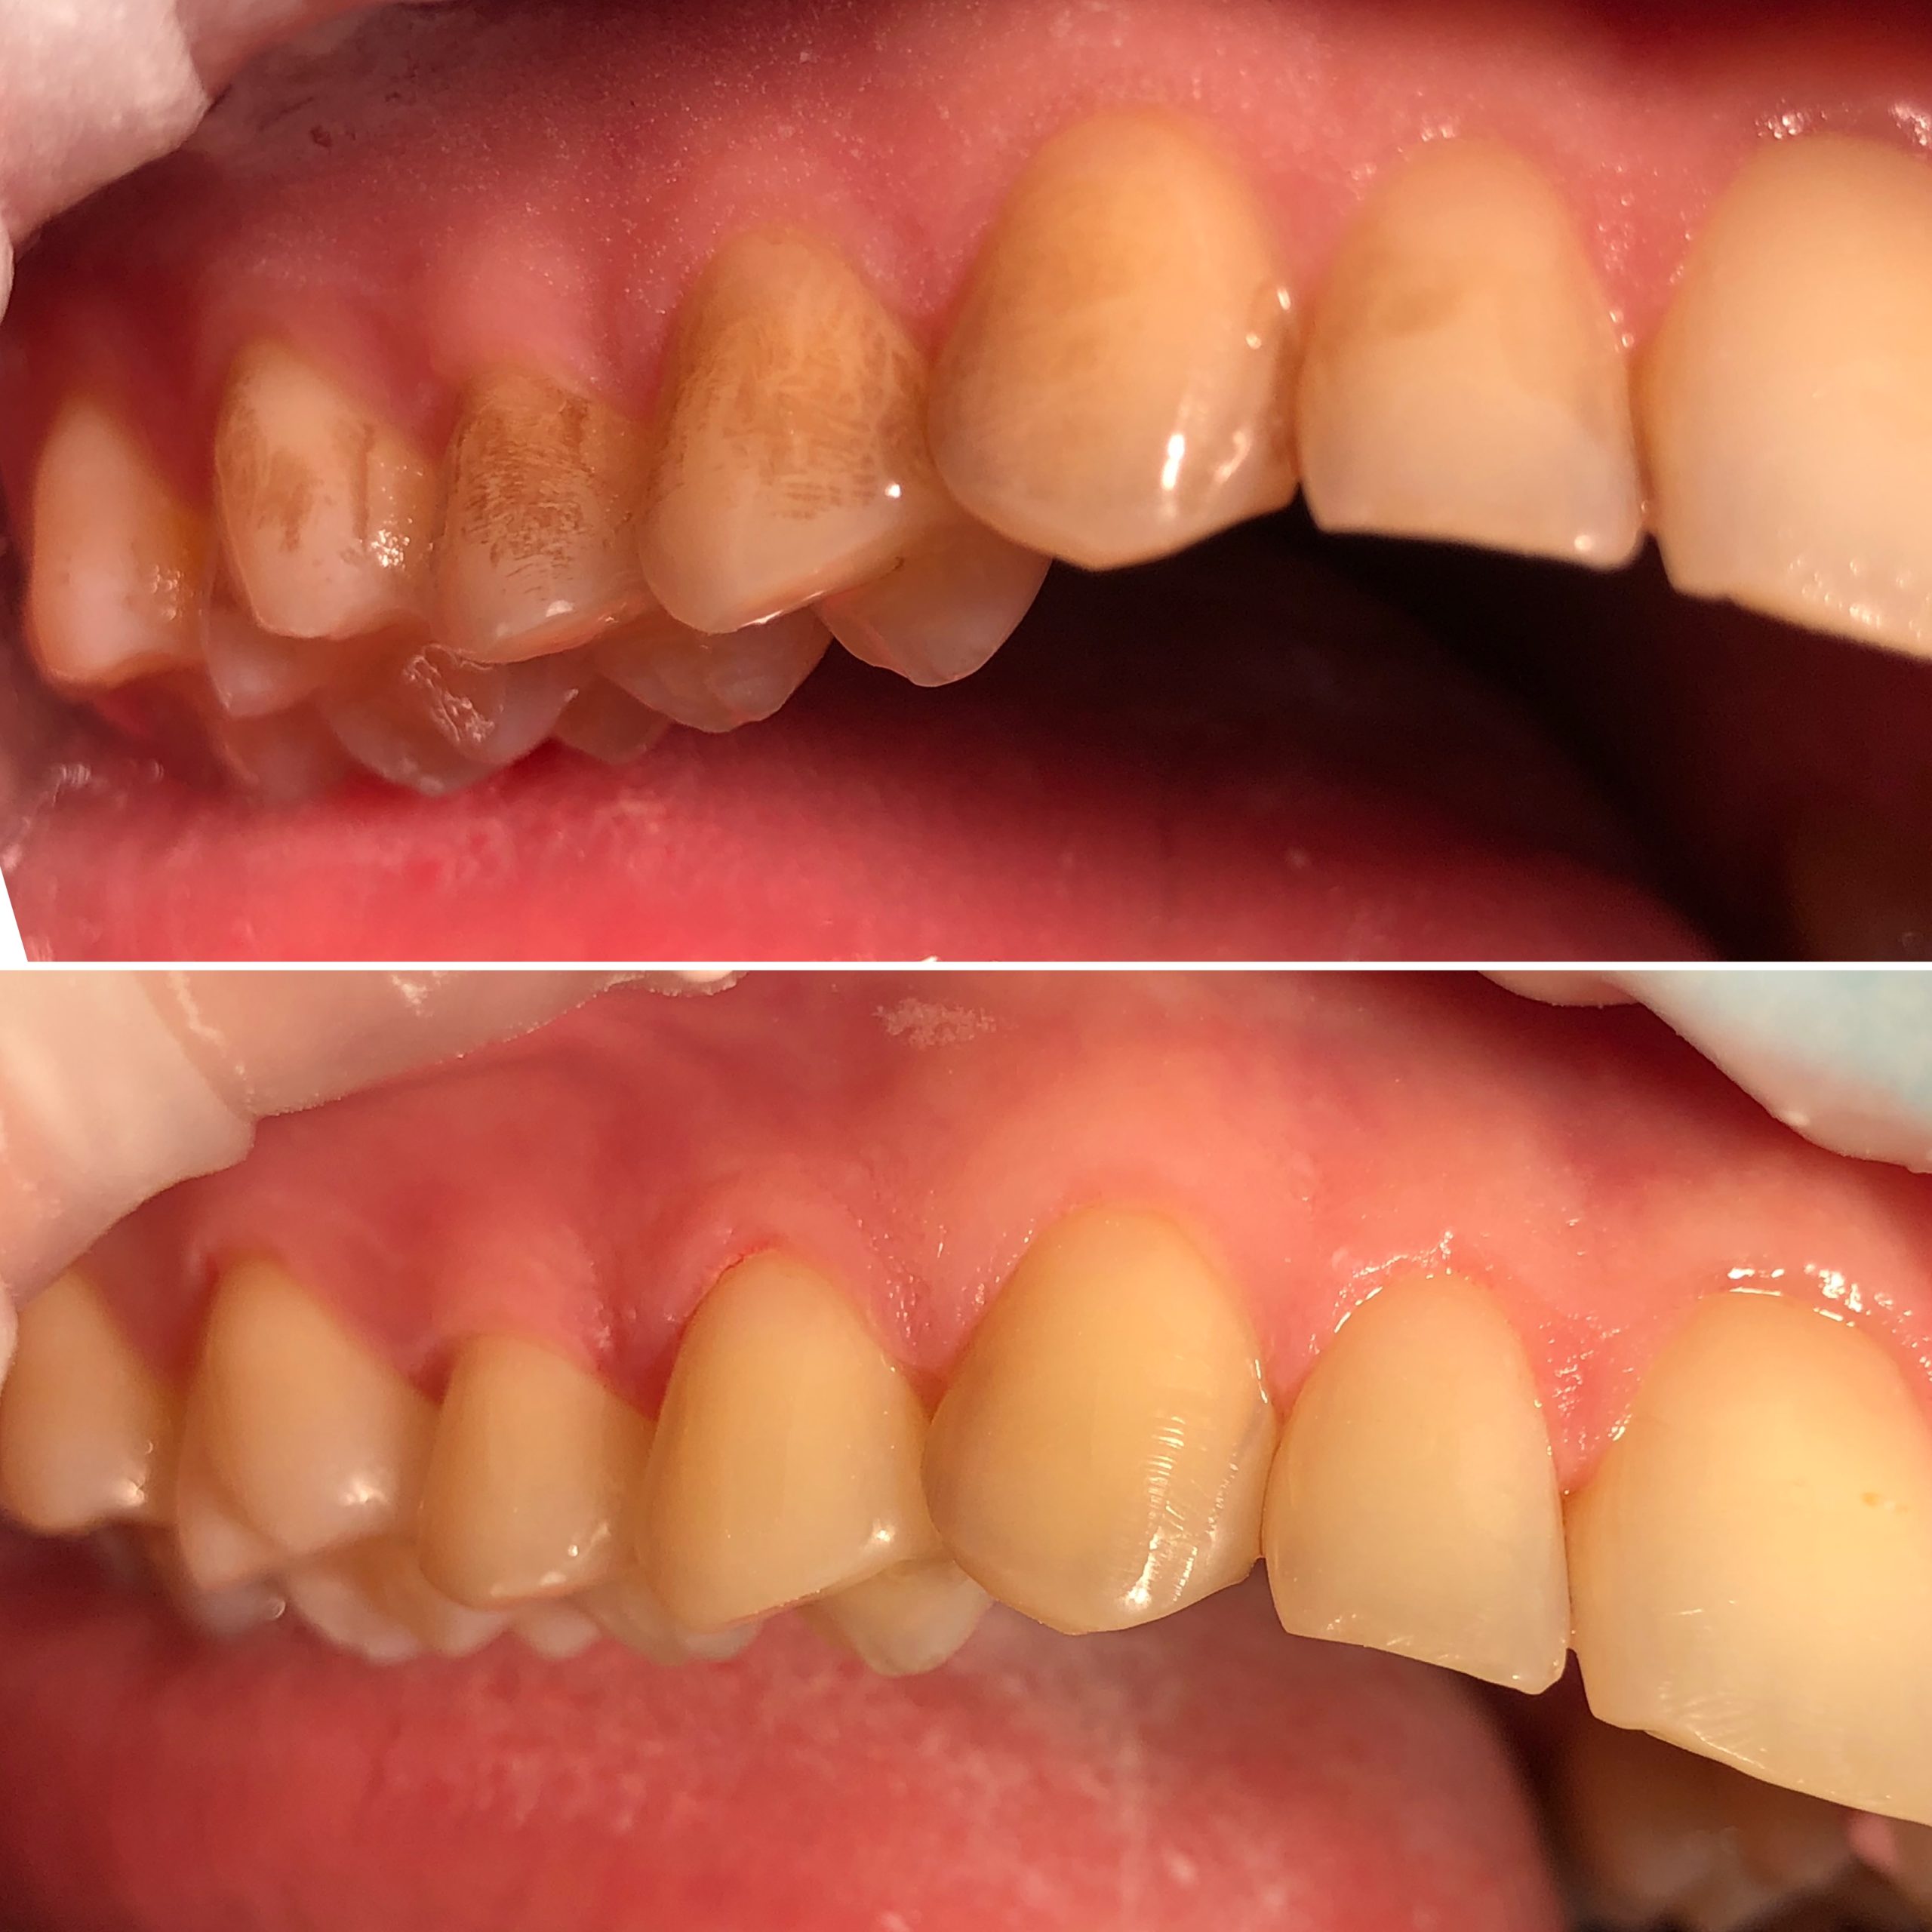

• Диагностика и лечение кариеса и его осложнений (пульпиты, периодонтиты)

• Художественная реставрация фронтального и бокового участка зубов

2023 год – «Прямая композитная реставрация фронтальной группы зубов» Владимир Мальченко